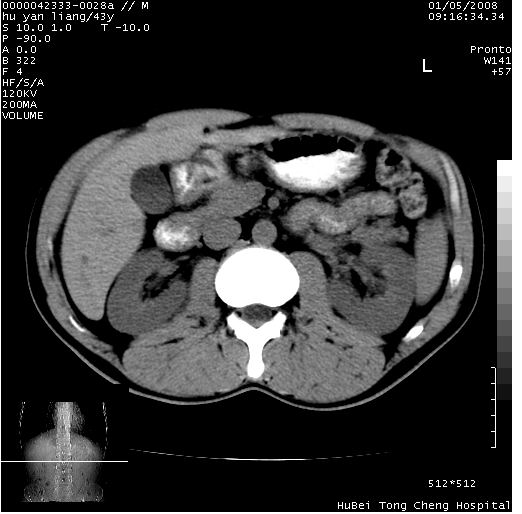

患者 男,43岁。右上腹不适1年余。既往有“肝右叶肝脓肿”病史,经保守治疗后痊愈。

b超提示:1)肝右叶肝内胆管结石。2)肝右叶占位性病变待排。

上中腹部ct轴位平扫+增强扫描(层厚10mm,螺距1.0,重建间隔10mm),图像如下:

肝右叶后段团块状钙化灶,结合病史考虑肝脓肿痊愈后表现。